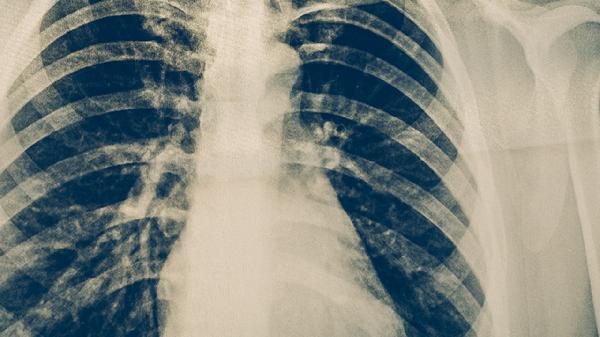

肺结节是否需要用药需根据病因决定。肺结节的治疗药物主要有抗生素如左氧氟沙星、抗结核药如异烟肼及靶向药物如吉非替尼,具体选择需结合结节性质与基础疾病。

药物使用需严格遵循医嘱,避免根据结节大小自行用药。直径超过8毫米的实性结节或存在毛刺征等恶性特征时,建议优先进行病理检查而非盲目用药。哺乳期患者禁用四环素类抗生素,哮喘患者慎用β-内酰胺类药物。

肺结节患者应每3-6个月复查胸部CT,观察结节变化。用药期间出现咯血、呼吸困难等症状需立即就诊。吸烟者必须戒烟,接触粉尘职业人群需加强防护。